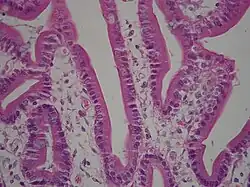

Гистология

Двенадцатиперстная кишка имеет особое гистологическое строение слизистой, делающее её эпителий более устойчивым к агрессивности как желудочной кислоты и пепсина, так и концентрированной жёлчи и панкреатических ферментов, чем эпителий дистальных отделов тонкой кишки. Строение эпителия двенадцатиперстной кишки отличается также и от строения эпителия желудка.

- В подслизистой основе двенадцатиперстной кишки (особенно в верхней её половине) располагаются дуоденальные (Бруннеровы) железы, по строению сходные с пилорическими железами желудка.

Двенадцатиперстная кишка собаки (X100)

Двенадцатиперстная кишка с амилоидными отложениями в собственной пластинке слизистой

Двенадцатиперстная кишка кошки (X60)

Микрофотография, показывающая лямблиоз на дуоденальной биопсии (H&E stain)- Двенадцатиперстная кишка с щеточной каемкой (микроворсинками)